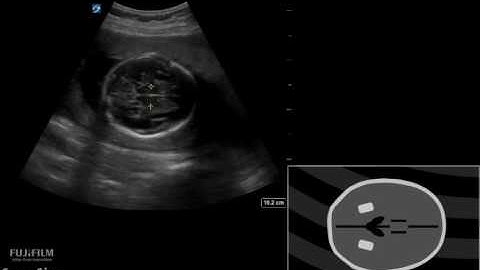

Fetal Biophysical Profile - Imaging Study Lecture